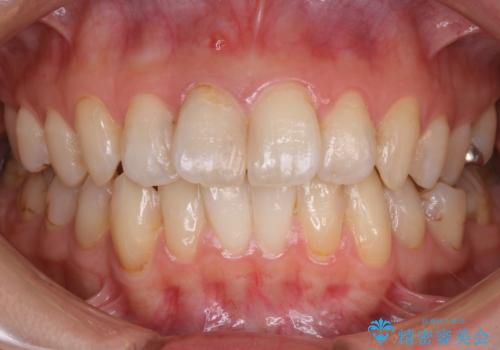

- 前歯のガタつきと噛み合わせの改善を希望してご来院されました。

目立たない装置での矯正治療をとのことでインビザラインを用いた非抜歯矯正を行うこととなりました。